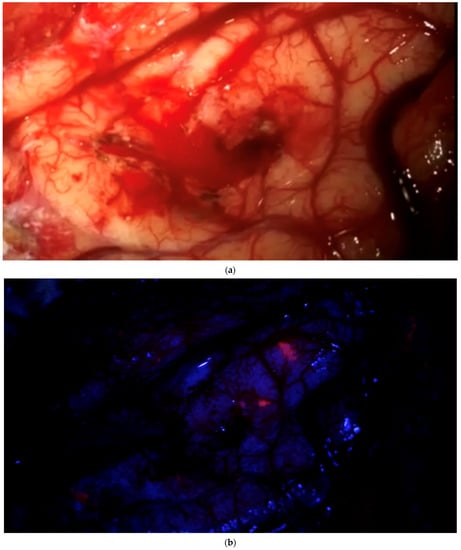

After clearing a field from tumor under white light, with the surgeon no longer being able to identify residual tumor in that field of view, the surgeon has the possibility of switching to blue light to determine whether any pathological tissue can be identified based on fluorescence. If the surgeon finds residual fluorescing tissue after switching to blue light, this area is pointed out using the neuronavigation pointer (and a navigation screenshot is taken). A biopsy is taken from the exact same region after switching back to white light if this can be performed safely. This procedure is also recorded by video from beginning to end. Such interrogations might be performed at multiple stages of surgery, provided a particular area (field of view) has been cleared of tumor according to the impression of the surgeon under white light. The interrogation of an inconspicuous bone flap also constitutes an “end of surgery” scenario if the surgeon wants to rule out any tumor infiltration in the bone. If any fluorescent bone is encountered, then this is biopsied prior to drilling of the bone flap (Figure 3).

“End of surgery” biopsy: After clearing a field from tumor under white light, with the surgeon no longer being able to identify residual tumor in that field of view, the surgeon switches to blue light to determine whether any pathological tissue can be identified based on fluorescence. Any fluorescing tissue is pointed out using the neuronavigation pointer (and a navigation screenshot is taken). A biopsy is then taken collected. This procedure is recorded by video from beginning to end. (a) After dissecting tumor from the brain, the brain is considered free of tumor. (b) Various areas of fluorescence can be observed. The surgeon would then resect the fluorescing tissue shown. (c) Navigation pointer and corresponding screenshot (“F”: footwards; “H”: headward; “A”: anterior; “P”: posterior; “L”: left; “R”: right).